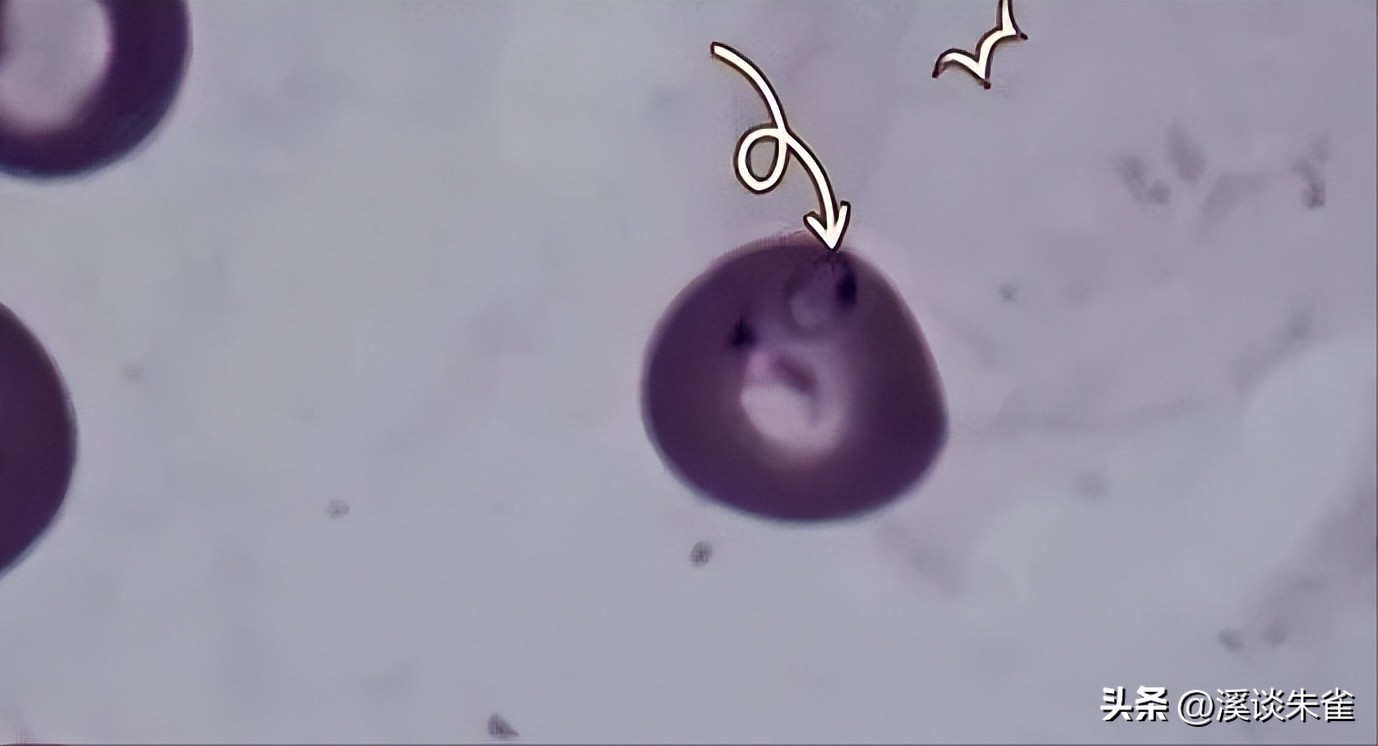

两个阴性对照(从健康牛供体和超纯水中提取的血液样本)和一个阳性对照(从牛血涂片中获得的样本,检测呈比格米纳双歧杆菌阳性,测试了附加文件 1:图像 S1)。

Brangus牛的平均(± SD)蜱计数高于Nellore牛(分别为45.5±20.9和10.08±2)(Mann-Whitney U检验, U (18)= 2148, Z = -8.07, P < 0.01) 。所有通过PCR和qPCR检测的样本均检测出比格米纳双歧杆菌阳性;相比之下,在PCR和qPCR测试的任何样品中都没有检测到牛双歧杆菌。